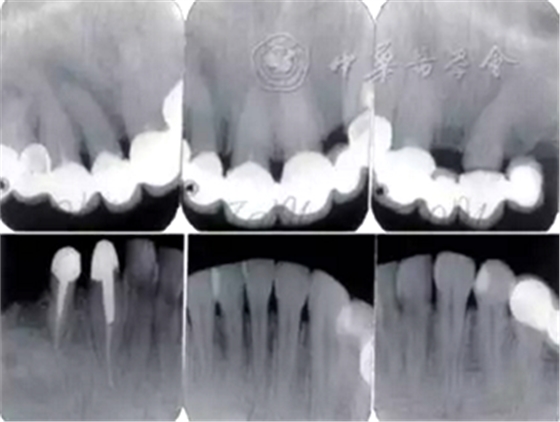

3.影像學(xué)檢查:

全口根尖X線片示鄰面骨嵴頂影像模糊;根管欠填、根充不致密,、未見根管治療影像,、根尖周可見低密度影像(圖2)。

圖2 患者初診時全口根尖X線片